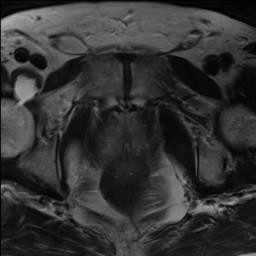

Modern deep neural networks struggle to transfer knowledge and generalize across diverse domains when deployed to real-world applications. Currently, domain generalization (DG) is introduced to learn a universal representation from multiple domains to improve the network generalization ability on unseen domains. However, previous DG methods only focus on the data-level consistency scheme without considering the synergistic regularization among different consistency schemes. In this paper, we present a novel Hierarchical Consistency framework for Domain Generalization (HCDG) by integrating Extrinsic Consistency and Intrinsic Consistency synergistically. Particularly, for the Extrinsic Consistency, we leverage the knowledge across multiple source domains to enforce data-level consistency. To better enhance such consistency, we design a novel Amplitude Gaussian-mixing strategy into Fourier-based data augmentation called DomainUp. For the Intrinsic Consistency, we perform task-level consistency for the same instance under the dual-task scenario. We evaluate the proposed HCDG framework on two medical image segmentation tasks, i.e., optic cup/disc segmentation on fundus images and prostate MRI segmentation. Extensive experimental results manifest the effectiveness and versatility of our HCDG framework.